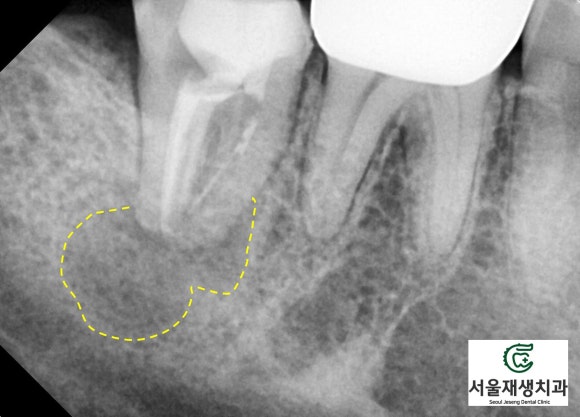

한 눈에 보기에도 병소의 크기가 꽤나 크지요?

치아가 뿌리 끝에 자기 몸뚱이만큼이나 큰 물혹을 달고 있습니다.

이러한 병소의 크기는 세균의 전체 수 및 세균종의 다양성과 비례합니다.

<병소가 큰 재신경치료 케이스의 비포 애프터>

(9개월 소요)